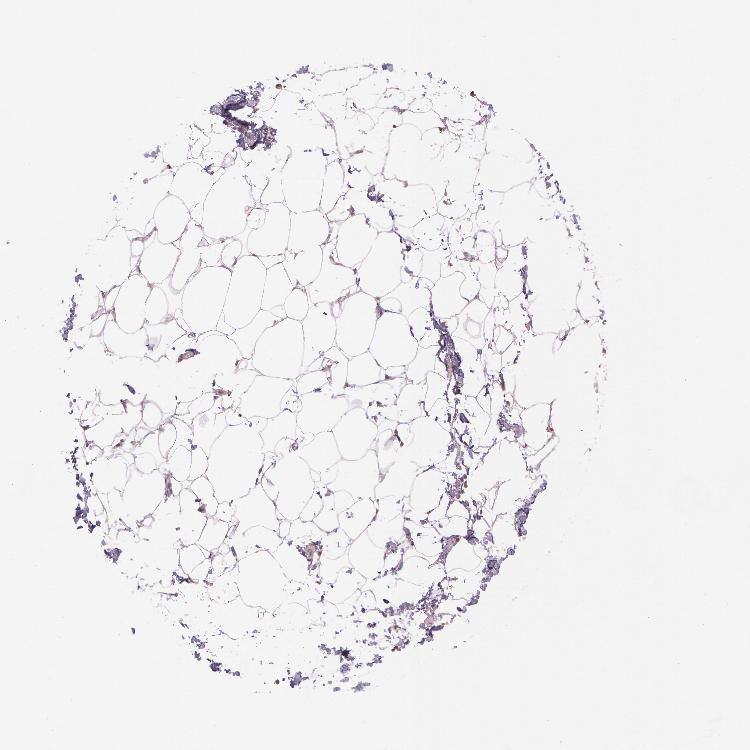

SOFT TISSUE 2 - Antibody stainingi

Antibody staining in the annotated cell types in the current human tissue is reported as not detected, low, medium, or high, based on conventional immunohistochemistry profiling in selected tissues. This score is based on the combination of the staining intensity and fraction of stained cells.

Each image is clickable and will lead to virtual microscopy that enables deeper exploration of all samples and also displays staining intensity scores, fraction scores and subcellular localization as well as patient and tissue information for each sample.

Antibody HPA001427Antibody HPA019665

Fibroblasts Not detectedNot detected

Peripheral nerve MediumNot detected